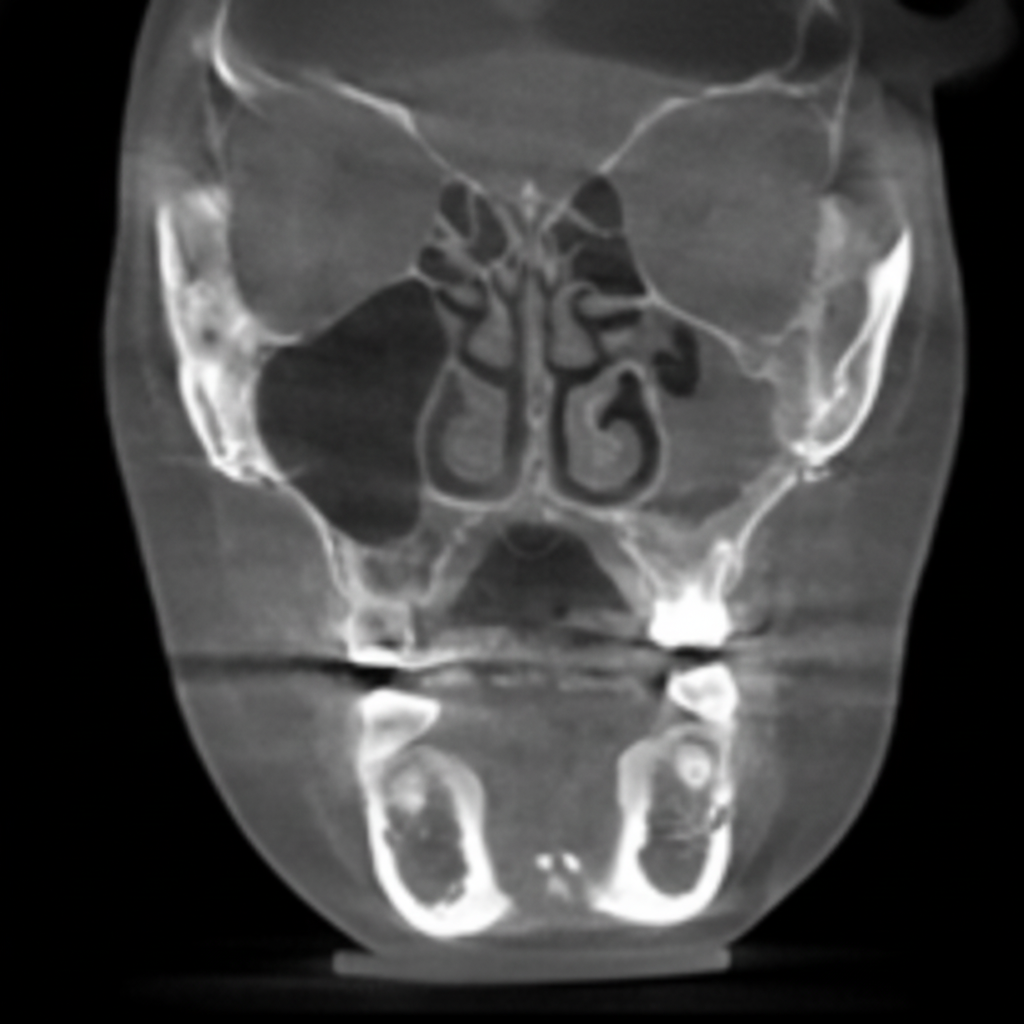

3D CT 분석에 의한 정밀진단

3D CT 분석을 통해 코뼈, 비중격, 연골길이, 내부변형 등 코 내부 상태에 대한 정확한 파악이 가능합니다.

코재수술의 경우 보형물의 위치, 고개기 대한 파악, 코골 연골과 변형 정도에 대한 예측을도 오차

다음 안정적인 결과를 도출합니다.

CT사진 1

3D-CT 정밀진단

3D-CT

정밀진단

겉으로 보이지 않는

코 뼈, 비중격 연골,

비대칭 유무 확인